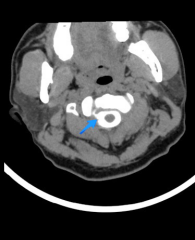

脑脊液水成像见颈2水平右侧脑脊液漏出;CTM脊髓造影见颈2水平右侧脑脊液漏出。

钟水生推断,可能是那次急刹车造成患者脊柱挥鞭样损伤,致脑脊液漏,引起低颅压综合征。